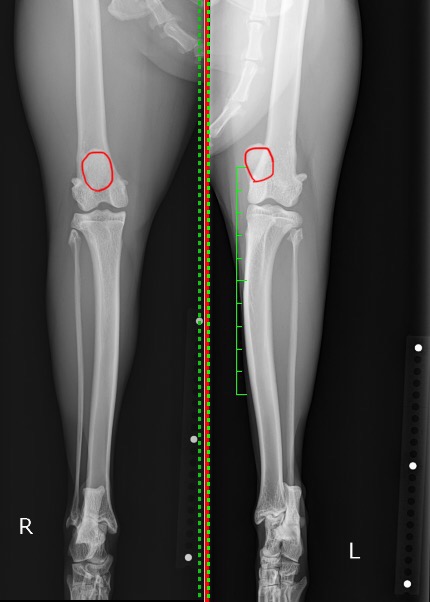

後肢を正面から撮影しているX線を見比べると、右後肢は膝蓋骨(赤丸)が大腿骨の中央に位置し滑車溝にはまっているのに対し、左後肢の膝蓋骨(赤丸)は内側に位置(内方脱臼)しているのが分かるかと思います。

各種検査より、この子の跛行の原因は膝蓋骨内方脱臼に起因するものと判断し、外科的に整復する事となりました。